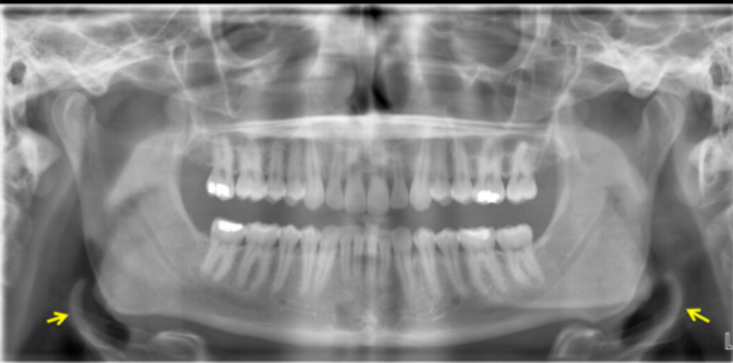

error

chin up